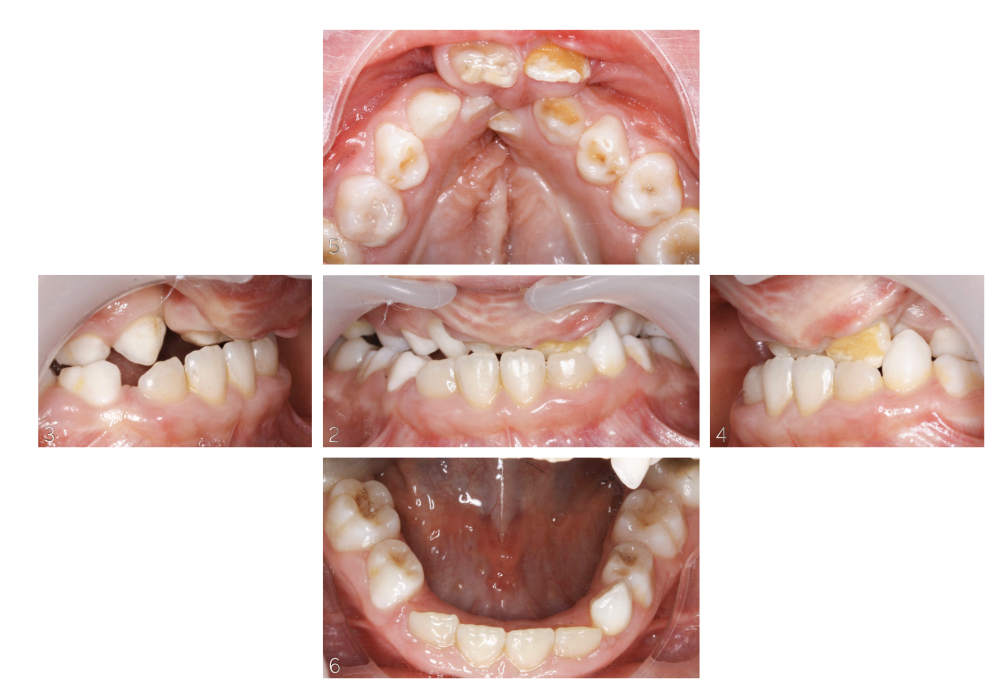

Ce patient atteint d’une fente labio-alvéolo palatine bilatérale a été reçu en consultation d’orthodontie à 5 ans (fig. 1-6). La première phase, d’expansion maxillaire, a été menée par disjoncteur en V. À l’issue, des greffes osseuses alvéolaires secondaires par apport de verre bioactif 45S5 (GlassBone®) ont été réalisées. Un quad-hélix maxillaire maintenait la dimension transversale en attendant l’évolution des dents permanentes (fig. 7-8). L’examen clinique a révélé une agénésie de la dent 22, une dent 12 riziforme et un odontome 22bis palatin.